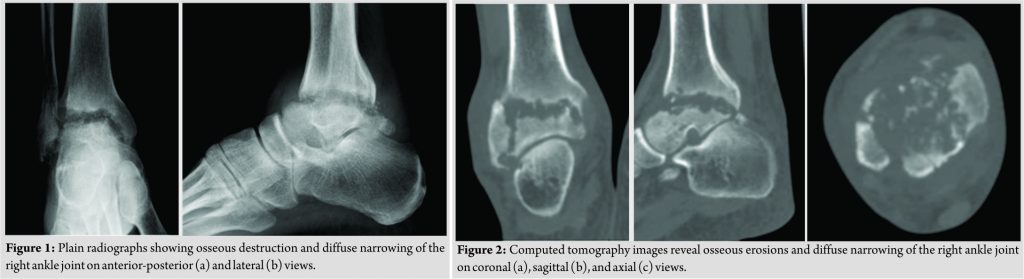

A 55-year-old man presented to our university hospital complaining of general fatigue for the past several months. 13 years earlier, he had undergone aorta valve replacement at our hospital for severe aortic regurgitation caused by infective endocarditis with aortic valve vegetations and had been receiving oral warfarin as an anticoagulant since that time. He was 167 cm tall, weighed 60 kg, and had a body mass index of 21.7. Laboratory investigations revealed severe anemia with hemoglobin of 4.4 g/dL, so he was admitted to the internal medicine department of our hospital for blood transfusion. He also reported a 5-year history of untreated right ankle pain that had worsened in the previous month. During this hospitalization, he was referred to our department for the assessment of the right ankle pain. On physical examination, there were tenderness, local warmth, and redness over the right ankle, especially on the anterior aspect, and range of motion at the ankle joint was limited to 0°of dorsiflexion and 5° of plantarflexion. Laboratory investigations revealed evidence of inflammation(white blood cell count 8600 cells/µL and C-reactiveprotein 8.44 mg/dL). Clinical examination showed no feature ssuggestive of congenital connective tissue disorder. Radiography and computed tomography images revealed osseous destruction and diffuse narrowing of the right ankle joint space (Fig. 1a and b and Fig. 2a, b, c).